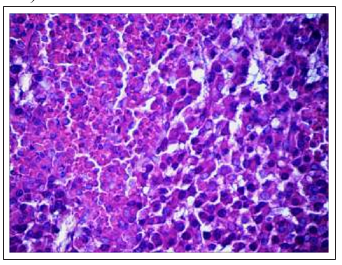

Thecharacteristic morphological distinction ofDDP-resistant Guerin’s carcinoma treated with Cisplatin-Ebewe® was that, on the background of the overall structure of the tumor, which did not differ from the control, certain cells with signs of treatment pathomorphism were detected (Fig. 11C). Along with this, there were the necrosis and necrobiosis fields of different sizes (Fig. 11 D). It should be noted that in all tumors exposed to Cisplatin-Ebewe® , a large number of mitoses, including pathological, were detected

Figure 11C: Formation of "giants of medical pathomorphosis" in the DDP-resistant Guerin’scarcinomaunderthe Cisplatin-Ebewe® influence (×200)

Figure 11D: Pattern of tumor cells with signs of necrobiosis (on the right) was bordered by a pattern of necrotic cells (on the left). Action of Cisplatin-Ebewe® (×200)

Fig.11 Changes in the cytoarchitectonics of DDP-resistant Guerin’s carcinoma under the influence of Cisplatin-Ebewe and Feroplat® (coloring with hematoxylin and eosin).